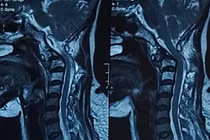

Ung thư tuyến giáp có tốc độ phát triển rất chậm với thời gian nhân đôi trên 1 năm, tiến triển tự nhiên thậm chí diễn ra trong nhiều thập kỉ. Ung thư tuyến giáp thường có khả năng điều trị cao khi được phát hiện sớm.

Sau khi cắt tuyến giáp bệnh nhân vẫn cần theo dõi phòng ngừa tái phát bên chưa cắt hoặc hạch. Cần biết cách theo dõi ung thư tuyến giáp và sau cắt 1 thùy tuyến giáp cho đúng.